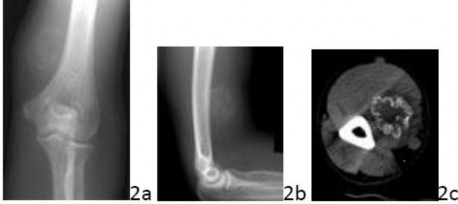

Question2 2a 2b 2c A 36-year-old man reports pain and fullness in the medial arm just proximal to the epicondyle. He denies trauma to the arm but noted some soreness following an arm wrestling match a few months ago. Figures 2a through 2c show the radiographs and a CT scan. What is the most likely diagnosis?

1. # Extraskeletal osteosarcoma

2. # Parosteal osteosarcoma

3. # Osteochondroma

4. # Myositis ossificans

5. # Synovial cell sarcoma

DISCUSSION: The radiographs reveal a mature lesion that is ossified, not calcified, in the soft tissues of the arm, which is juxtaposed to the bone but not sessile ("stuck on") on the cortex nor does the lesion share the cortex. The CT scan reveals a soft-tissue lesion that is mineralized at the periphery, not centrally. This combination of features (smooth, ossified soft-tissue mass with mineral density at the periphery, known as the Zonation Phenomenon of Ackerman) strongly suggests myositis ossificans as the diagnosis. Osteosarcoma would mature in the central areas, not the periphery, and would not have this smooth appearance. Parosteal osteosarcoma would be attached to the cortex (this is not a good location for that diagnosis), osteochondroma would share the bony cortex, and synovial sarcoma generally presents with whispy, irregular calcification within the mass. The images do not support any of these other diagnoses. The Preferred Response to Question # 2 is 4.